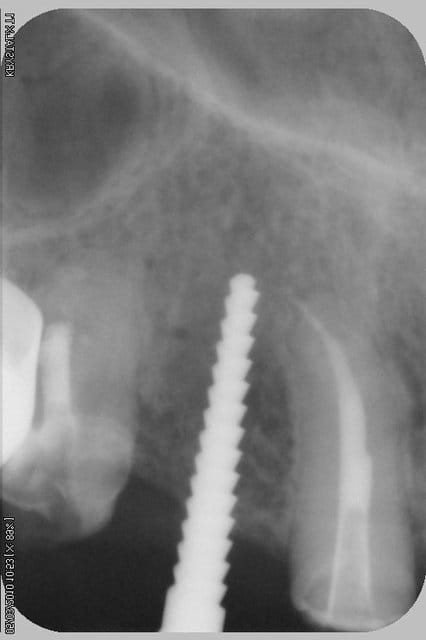

tiens...un ptit cas...

dans ce petit cas...j'ai commencé avec le kit MIS...et fini ma voie crestale avec le kit HBS...

ok, c'est un mini soulevé...mais bon , c'est un exemple...

juste une précision...premier foret 1.3mm sur 8mm...expansion pour mettre un implant de 4x10...

j'ai juste "léché" la préparation du site final avec le foret terminal du système...sur 8mm...avant d'insérer l'implant...stab primaire au top...blocage à 40 Ncm...